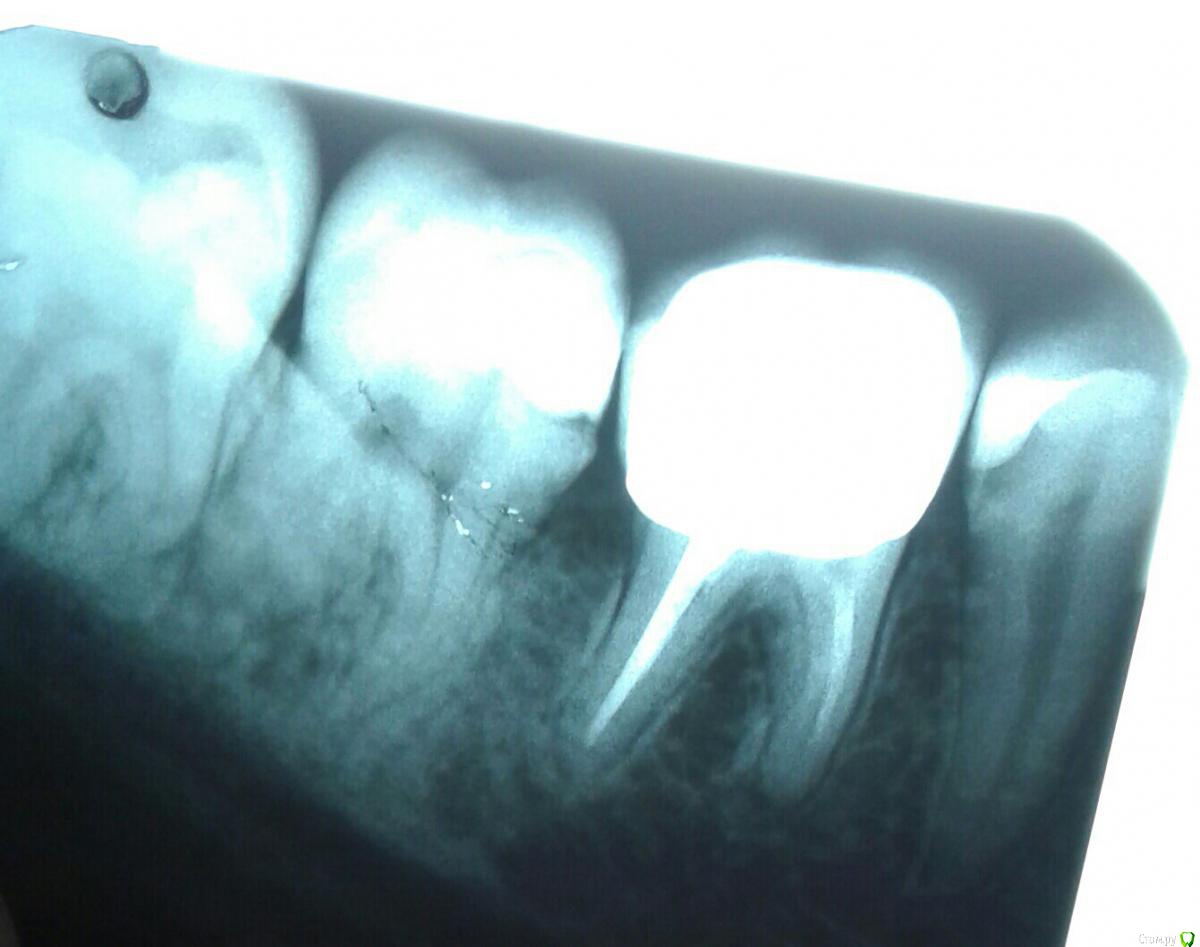

kramer Опубликовано 27 июля, 2018 Поделиться Опубликовано 27 июля, 2018 (изменено) Да банально пульпит нижней семерки. Там кариес под пломбой, видно же. Изменено 27 июля, 2018 пользователем kramer 1 Ссылка на комментарий

red_butler Опубликовано 27 июля, 2018 Поделиться Опубликовано 27 июля, 2018 Да банально пульпит нижней семерки. Там кариес под пломбой, видно же. тут кандидатов на пульпит прорва 2 Ссылка на комментарий

kramer Опубликовано 27 июля, 2018 Поделиться Опубликовано 27 июля, 2018 Про пульпит я у всех трех врачей с самого начала спрашивала, все его отрицают, так как нет реакции на холодное, горячее, воздух, зуб не болит все это время, появилась только реакция по накусывание и простукивание. По Вашему мнению нужно удалить нерв в семерке и боль пройдет? Как и сказано было выше, я насчитал с этой стороны 5 зубов, которые могут давать такую симптоматику, но из них 7ка наиболее вероятно. Ссылка на комментарий

Инна2106 Опубликовано 27 июля, 2018 Автор Поделиться Опубликовано 27 июля, 2018 На снимке не могу понять, в семерке как не видно одного корня зуба (я про что в 6-ке и 8ке их два, а в 7-ке один и второй как пятно). Что это означает?Как и сказано было выше, я насчитал с этой стороны 5 зубов, которые могут давать такую симптоматику, но из них 7ка наиболее вероятно. Ссылка на комментарий

kramer Опубликовано 27 июля, 2018 Поделиться Опубликовано 27 июля, 2018 На снимке не могу понять, в семерке как не видно одного корня зуба (я про что в 6-ке и 8ке их два, а в 7-ке один и второй как пятно). Что это означает?Сорри, не понял ваш вопрос. Все видно, 2 корня. Ссылка на комментарий

Инна2106 Опубликовано 27 июля, 2018 Автор Поделиться Опубликовано 27 июля, 2018 (изменено) когда смотришь на снимок зубов два корня и два канала, на 6 и 8-м зубах это четко видно в 7-м один видно второй не ясно где, визуально. Эта трещина на снимке под пломбой и есть кариес?Сорри, не понял ваш вопрос. Все видно, 2 корня. Изменено 27 июля, 2018 пользователем Инна2106 Ссылка на комментарий

kramer Опубликовано 27 июля, 2018 Поделиться Опубликовано 27 июля, 2018 (изменено) когда смотришь на снимок зубов два корня и два канала, на 6 и 8-м зубах это четко видно в 7-м один видно второй не ясно где, визуально. Эта трещина на снимке под пломбой и есть кариес? Я не знаю, куда вы смотрите, но мне видно все Трещина на снимке не может быть определена. А вот кариес видно. Он прям под пломбой. Изменено 27 июля, 2018 пользователем kramer Ссылка на комментарий